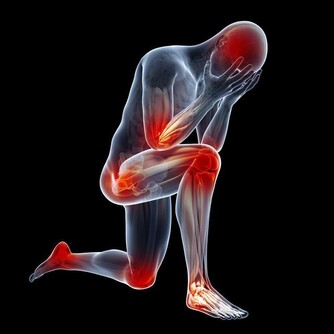

氨基酸是構成蛋白質的基本單位,有研究表明,老年人與中青年人相比,在同等的營養條件下,老年人的支鏈氨基酸減低得更為明顯,這直接影響身體肌肉量。